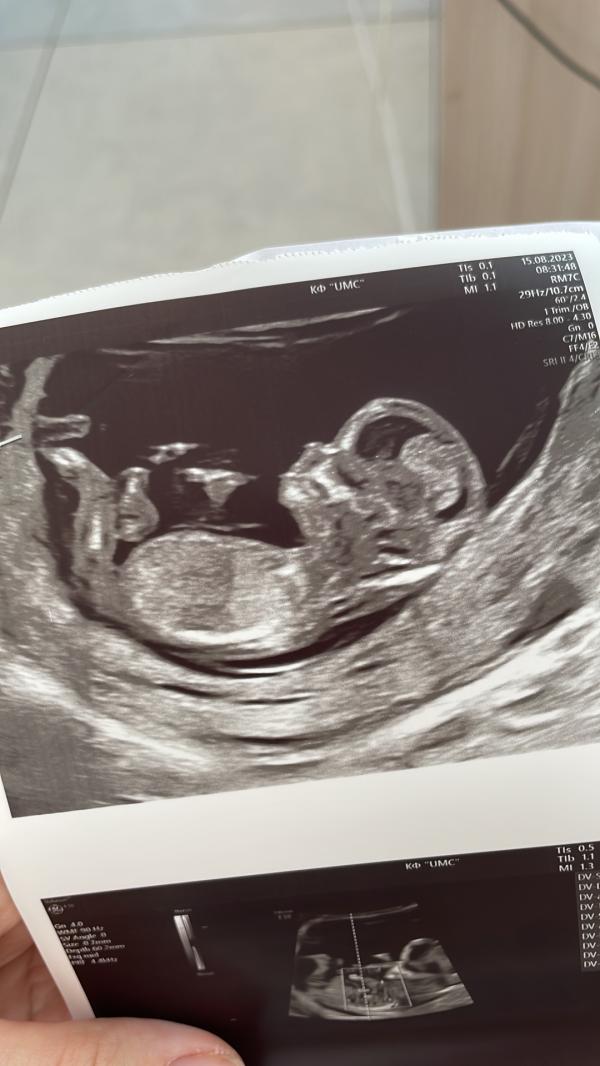

Первый скрининг )

Альхамдулиллах все хорошо, развивается отлично. А то переживала после антибиотиков как будет. Только вот пол не сказали ну может девочка говорит. Честно немного расстроилась я с первой беременности мечтала о мальчике🥲, я всегда хотела мальчика воспитать его настоящим мужчиной, покупать ему красивые рубашки костюмы, а когда он вырастит влюбиться помогать ухаживать за девочкой, выбирать вместе подарки. Почему то мне всегда кажется что мальчики больше секретничают с мамами. Ну и ...